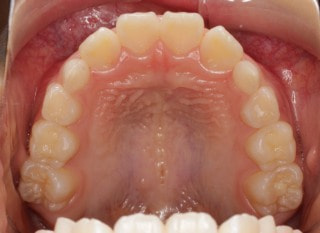

小児期の第二段階

治療中